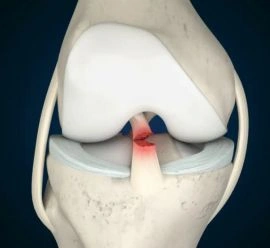

ACL and PCL Reconstruction

Anterior Cruciate Ligament (ACL) and Posterior Cruciate Ligament (PCL) reconstructions are critical surgeries.